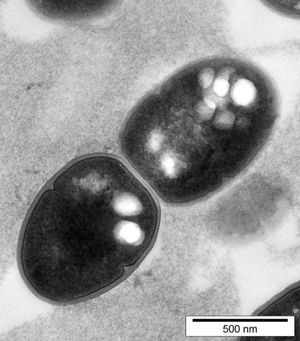

A microscope image of bacteria containing biobeadsAt Massey University, Bernd Rehm and his team at PolyBatics are using bacteria as factories to produce tiny bioplastic beads which are genetically engineered to display designer molecules on the surface. These molecules are disease-specific antigens so when they are injected into the body they can generate immunity. Some of the vaccines being developed could innoculate against diseases like tuberculosis, pneumonia and meningitis, however clinical trials are required before they can be used in humans.

A microscope image of bacteria containing biobeads.